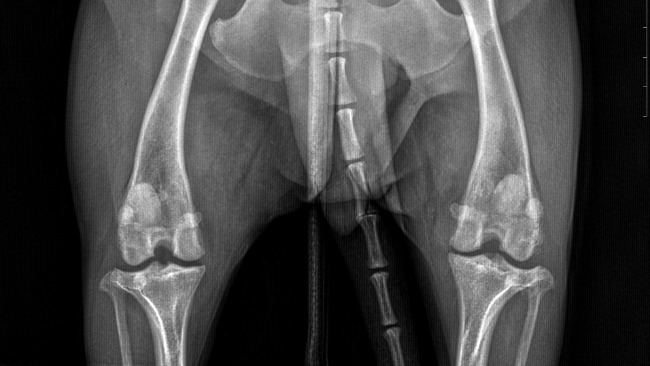

Kochani moje potrzeby schodzą na drugi plan. Moja sunia potrzebuje waszej pomocy. Eti musi przejsc operacje oraz leczenie, na które mnie niestety mnie niestac. Mogę jeździć na starym wózku, ale moi członkowie rodziny są dla mnie najważniejsi. Jestem gotowa zrezygnowac ze wszystkiego by jej pomóc.